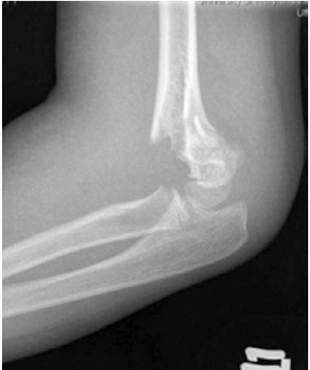

Hình 3.1.3: A,B : Phim chụp khớp khuỷu bệnh nhân nữ 10 tuổi gãy trên lồi cầu xương cánh tay độ III. C,D: Phim trong mổ của cùng bệnh nhân nắn chỉnh và cố định ổ gãy. Hai đinh Kirschner được sử dụng để làm vững cột ngoài, và một đinh Kirschner sử dụng để làm vững cột trong